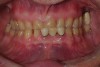

Figure 3  Preoperative view. Note the worn incisal edges and end-on-end occlusal relationship requiring an increase in OVD to restore.

Figure 3